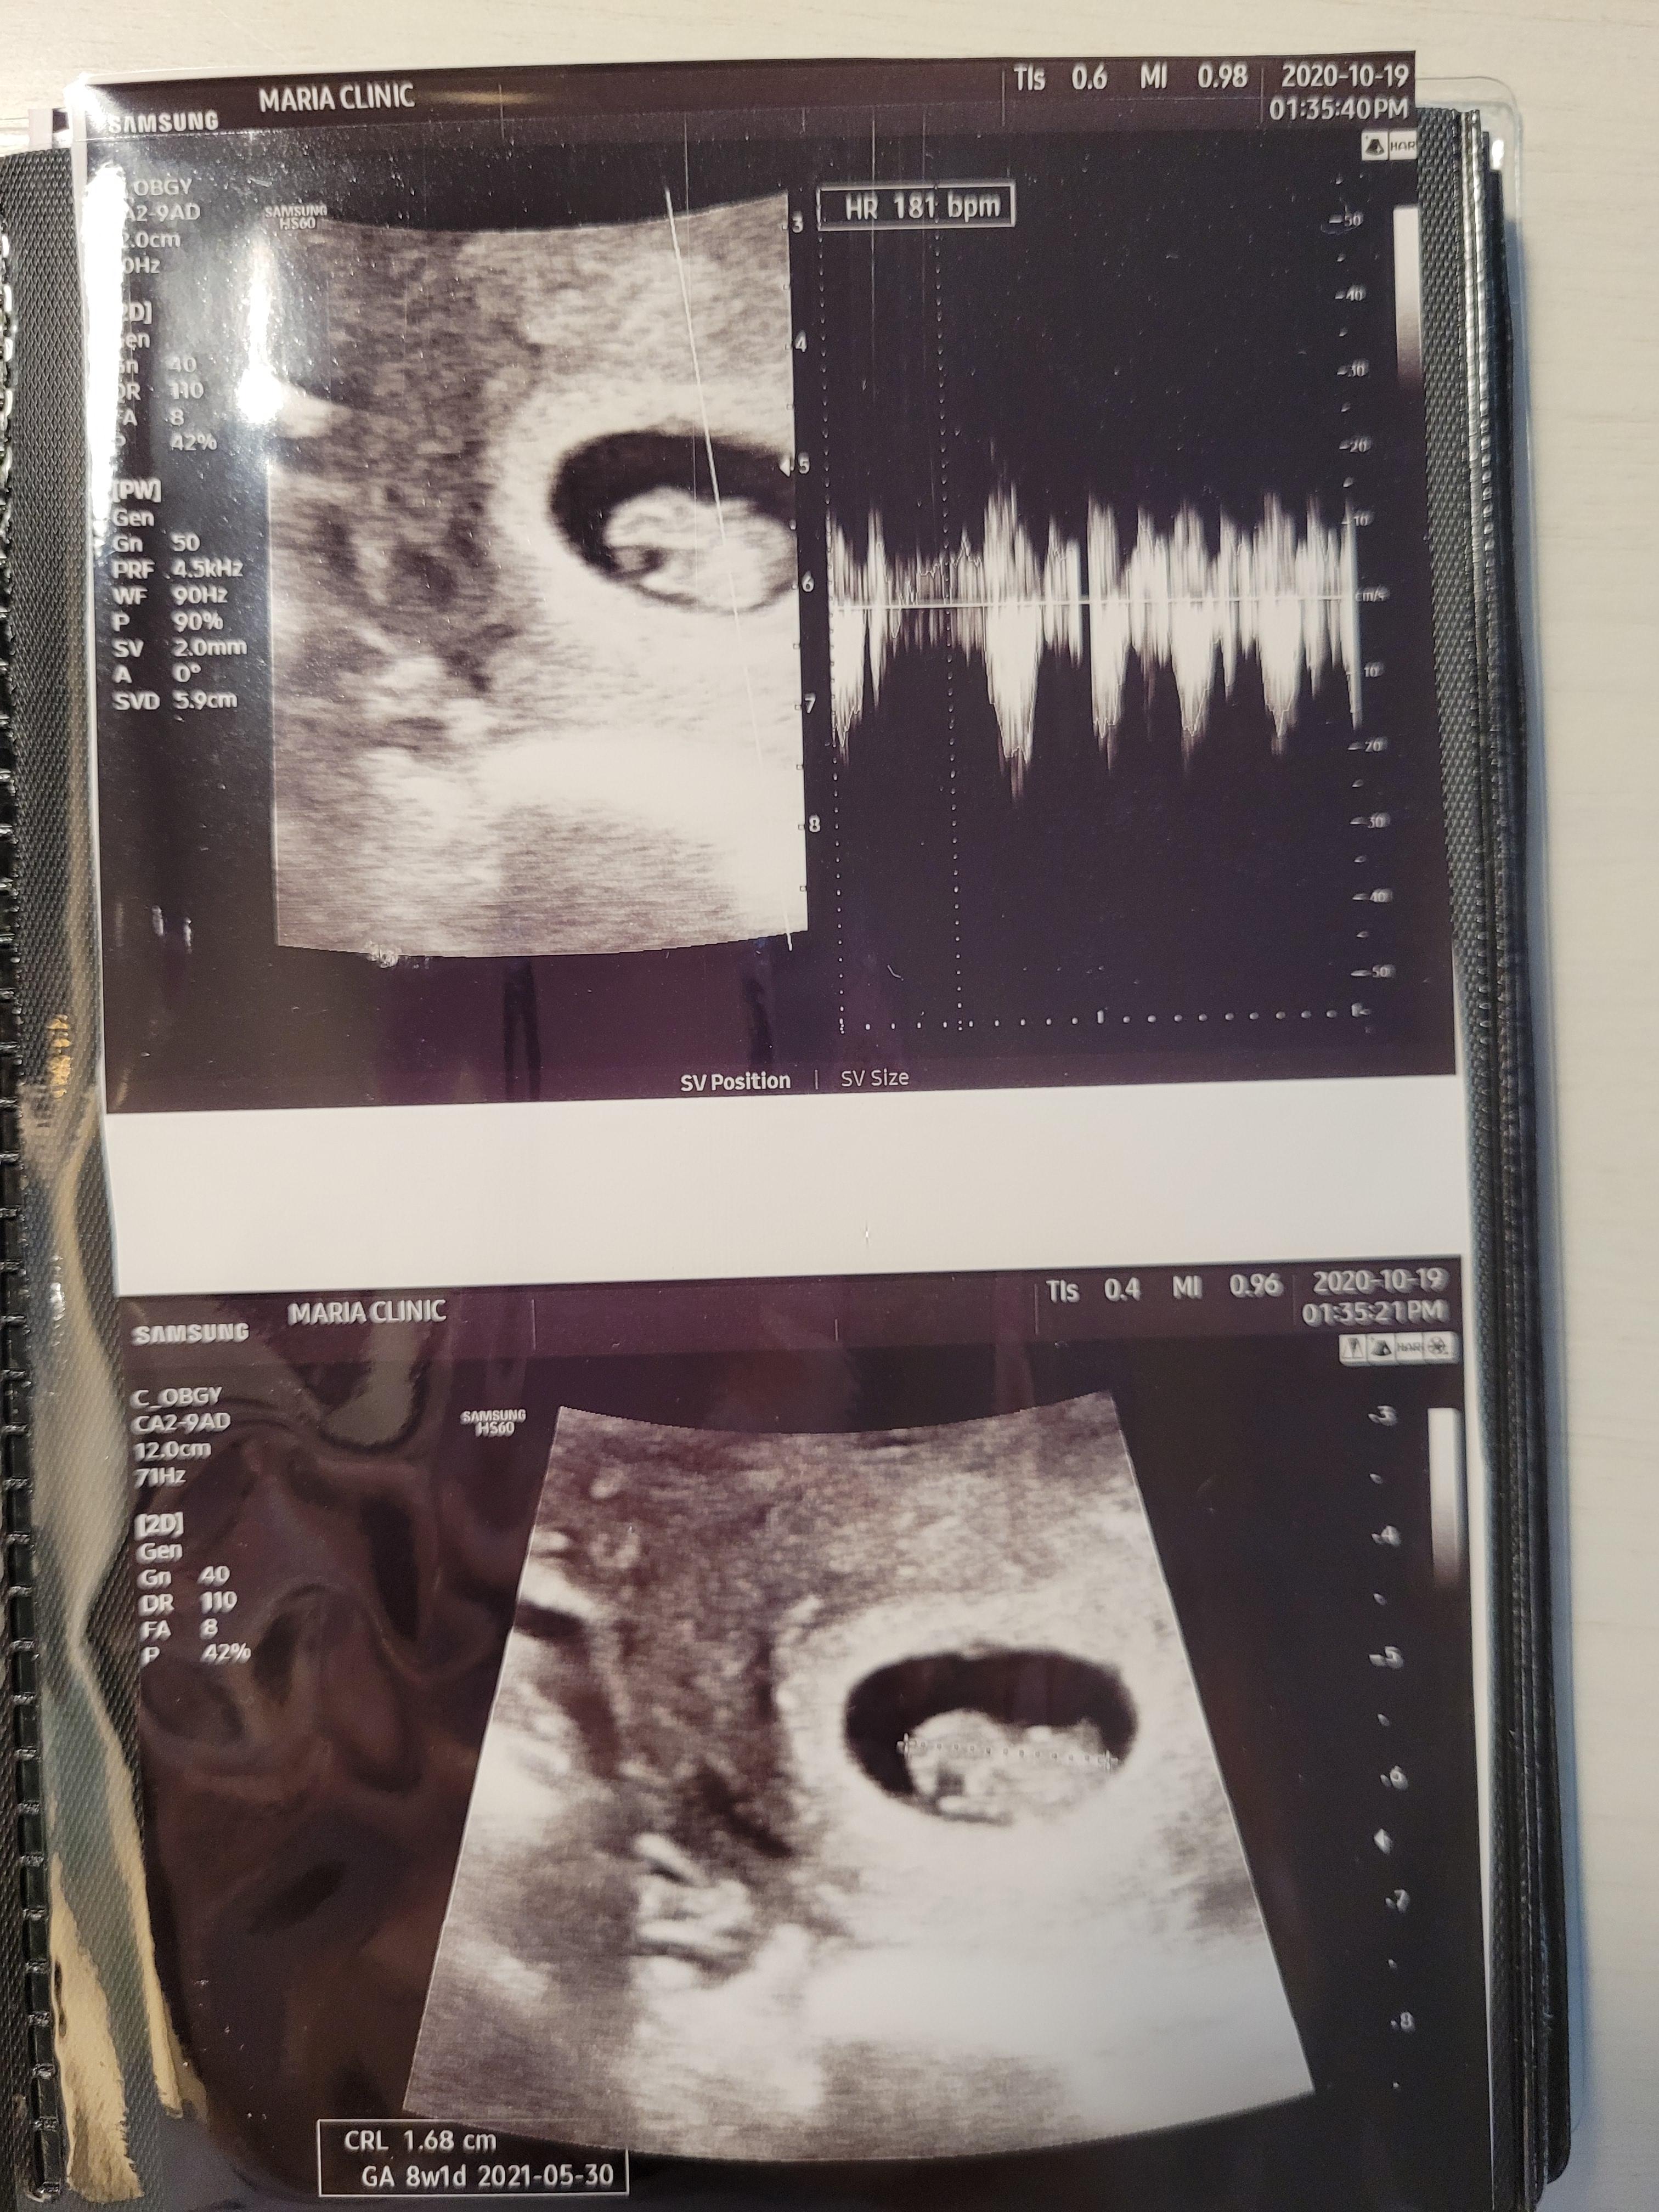

임신 8주 0일 평촌마리아 검진

임신 8주차 검진이에요.

이날은 아기가 1.68cm, 주수에 맞게 잘 크고있네요. ㅎㅎ

심장박동수도 괜찮고, 건강하게 잘 크고 있는것 같았어요.

매주 검진받을때 두근두근하고, 심장박동수는 주수에 맞는지 검진후에 확인하면서 집에 왔네요.